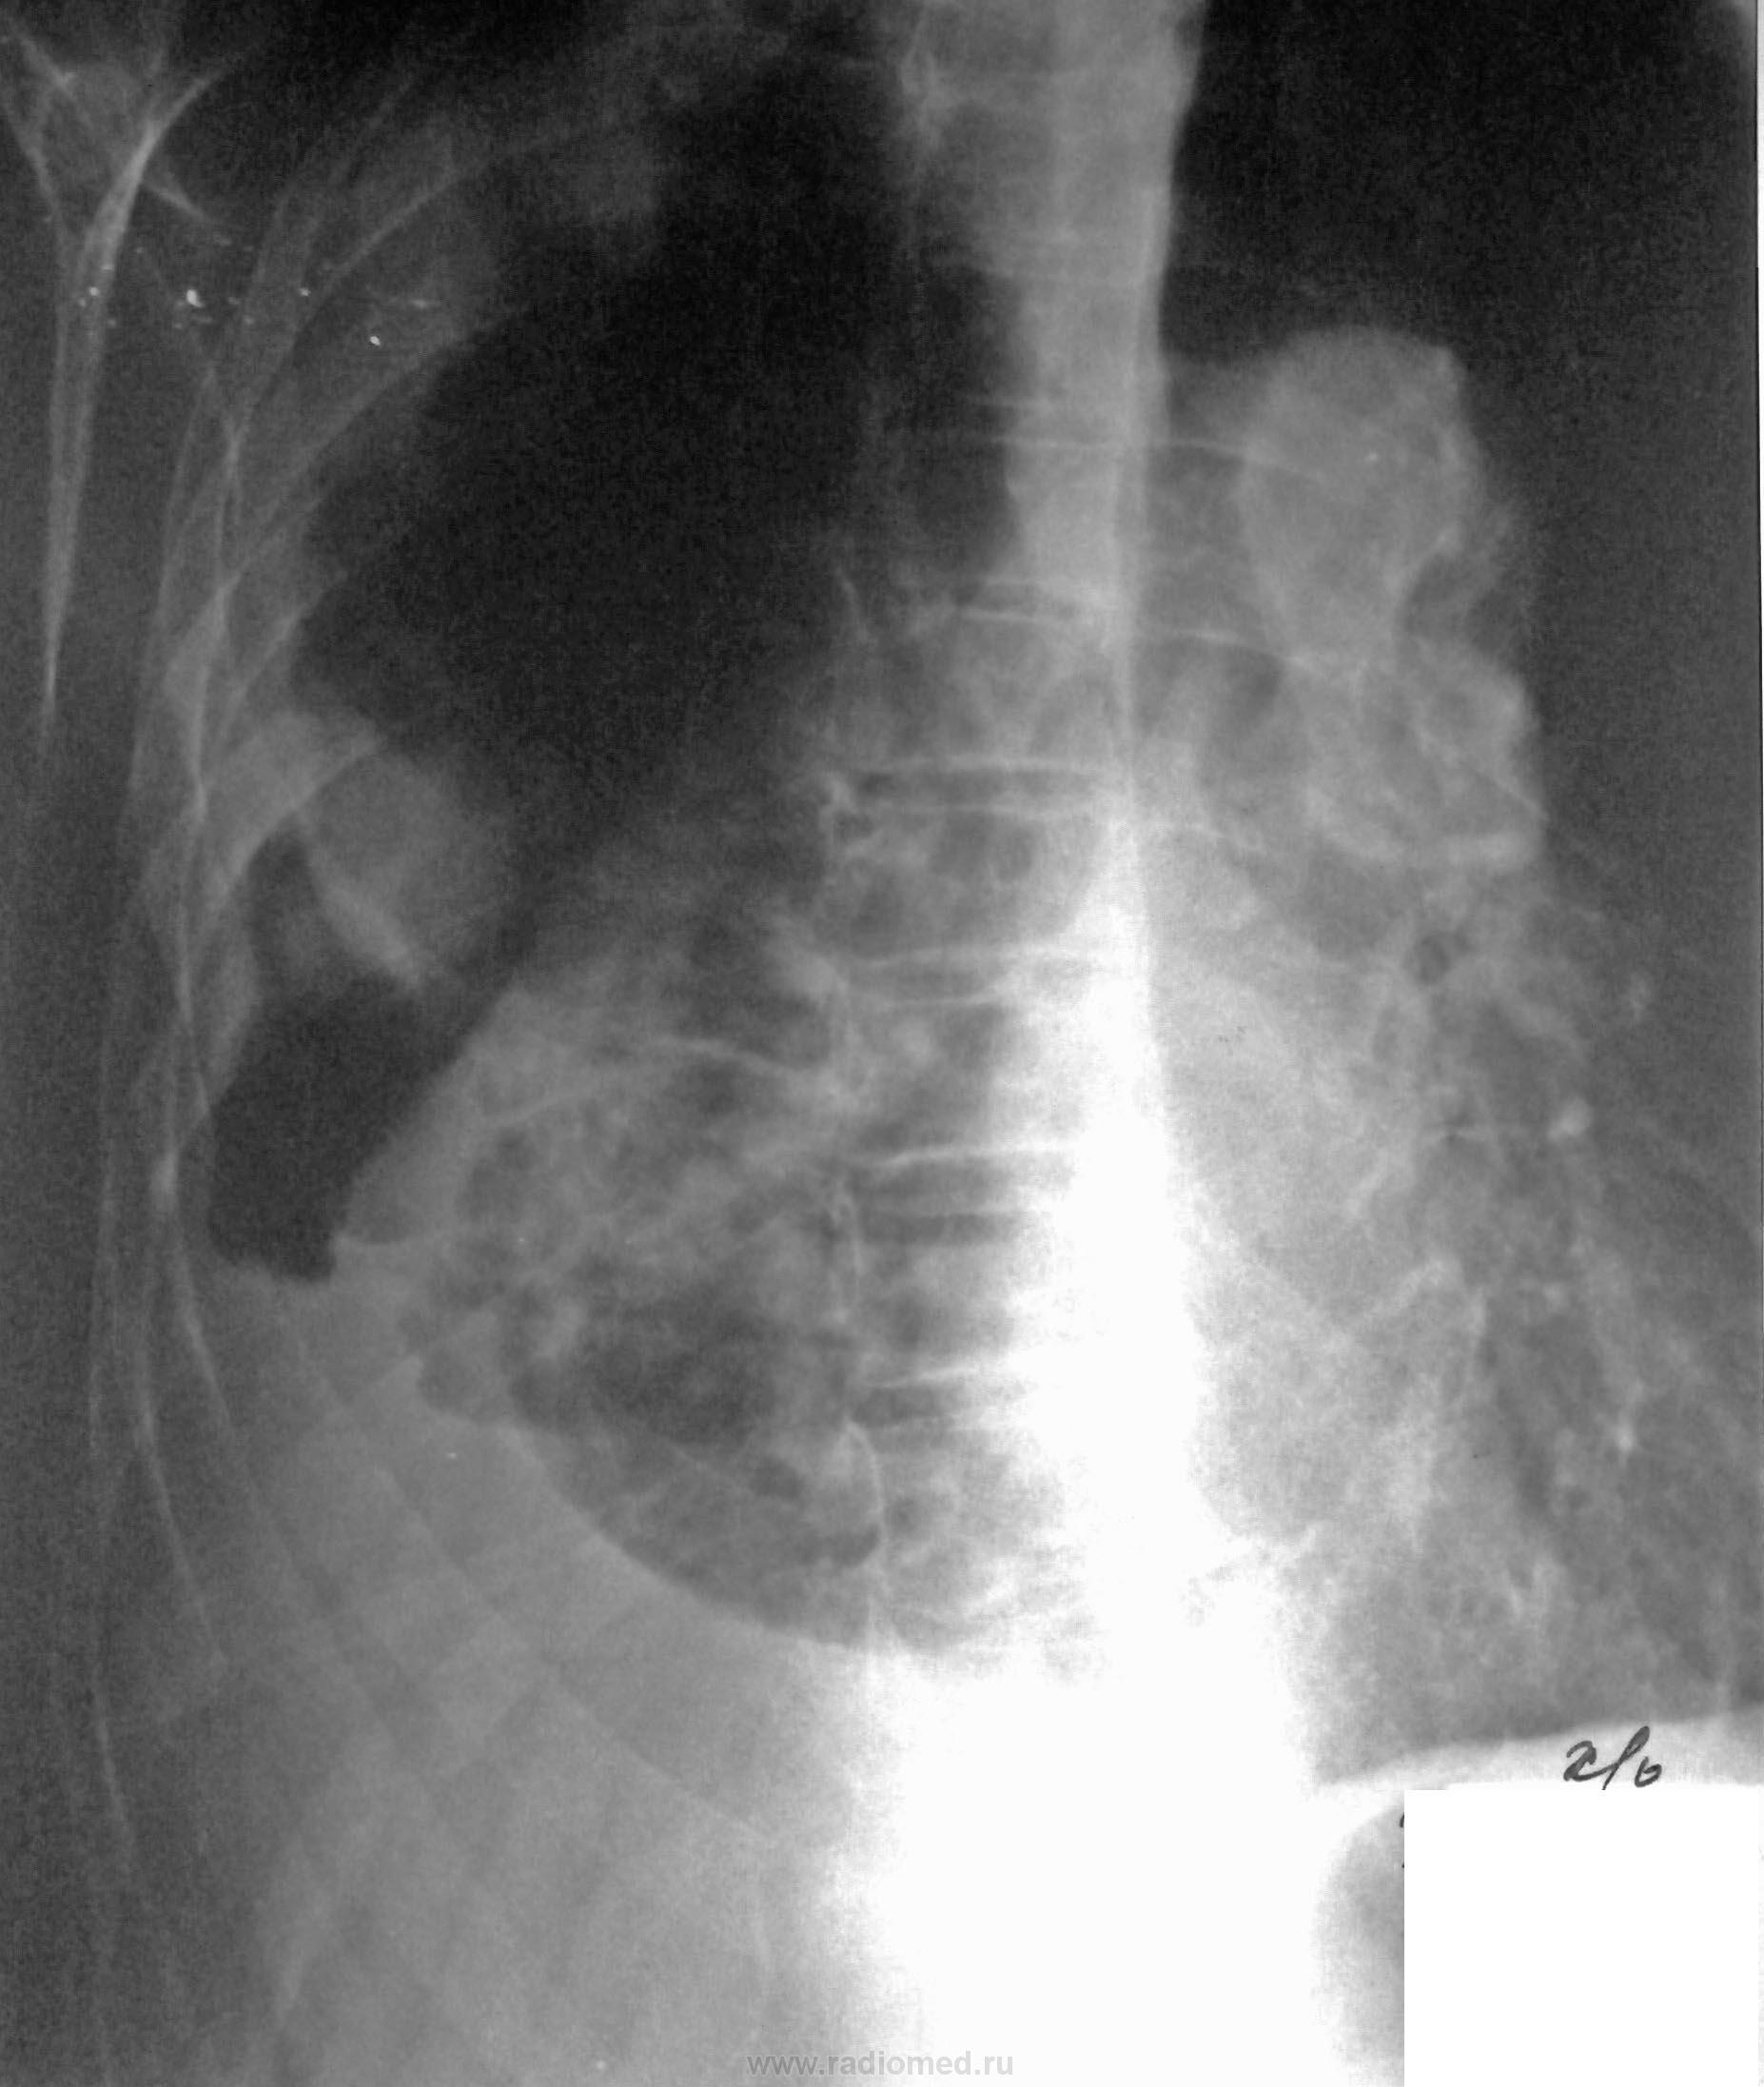

После плевральной пункции проведено контрольное рентгенологическое обследование.

Не могу разобраться, что за уровни жидкости на рентгенограммах при контрольном исследовании, возможно жидкость между плевральными спайками? Какова природа гидроторакса? Очень интересно ваше мнение…

злокачественное поражение плевры.

Присоединяюсь к предыдущим постам. Онкология.

Мне тоже не ясно это за полость, вопрос с образованием решен, но что за уровни жидкости?

Развитие пневмогидроторакса после плевральной пункции, на фоне спаечного процесса?

Серозно-геморрагическая жидкость = c-r

Очень похоже на мезотелиому. Особенно с учётом эвакуированной жидкости.